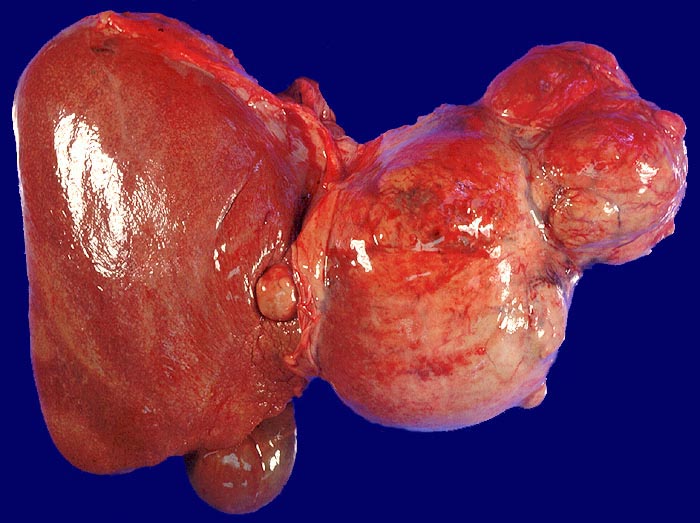

Makroskopisch imponiert das hepatozelluläre Karzinom als solitäre grosse Tumormasse, als zahlreiche zirrhoseartige Knoten oder als scharf begrenzter Knoten mit oder ohne Kapsel. Die tumorfreie Leber ist in der Mehrheit der Fälle zirrhotisch umgebaut. Mikroskopisch bilden die Tumorzellen mehr als 2 Zellen breite Trabekel (> 1237), kompakte Tumormassen (> 1229) oder pseudoglanduläre Strukturen (dilatierte Canaliculi) (> 1212) (> 1199). Desmoplastisches Bindegewebe fehlt meist. Innerhalb des Tumors fehlen Portalfelder. Es finden sich lediglich Arterien. Etwa bei der Hälfte der Karzinome lässt sich intrazytoplasmatische oder intracanaliculäre Galle (> 1238) nachweisen. Immunhistochemisch lassen sich mit einem polyklonalen Antikörper gegen Carcinoembryonales Antigen (CEA) Gallecanaliculi zwischen den Tumorzellen nachweisen. Die Tumorzellen bilden keinen Schleim.

• Scharf begrenzter bekapselter Tumor.

• Innerhalb des Tumors Blutgefässe, aber keine Portalfelder.